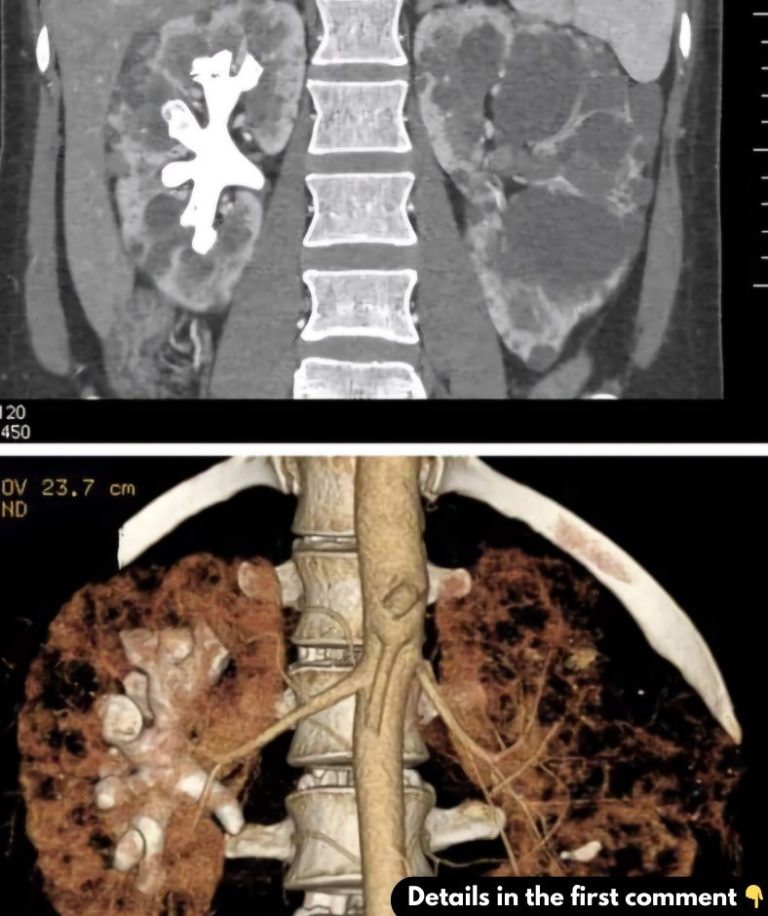

What Are Staghorn Kidney Stones?Staghorn kidney stones are named for their antler-like shape. These stones can become large and branch out, occupying the kidney’s renal pelvis and spreading into the calyces, which are the cavities that collect urine. They are typically made of magnesium ammonium phosphate, also known as struvite, and often result from recurrent urinary tract infections (UTIs). These stones are more common in women than men and pose a significant challenge due to their size and location. Unlike smaller stones that can pass naturally, staghorn stones usually require surgical treatment and can cause serious kidney damage if left untreated.

1.Imaging Tests: CT scans, X-rays, and ultrasounds are common imaging tools used to locate and assess the size of the stones. CT scans offer detailed images, making them particularly useful for diagnosing staghorn stones.